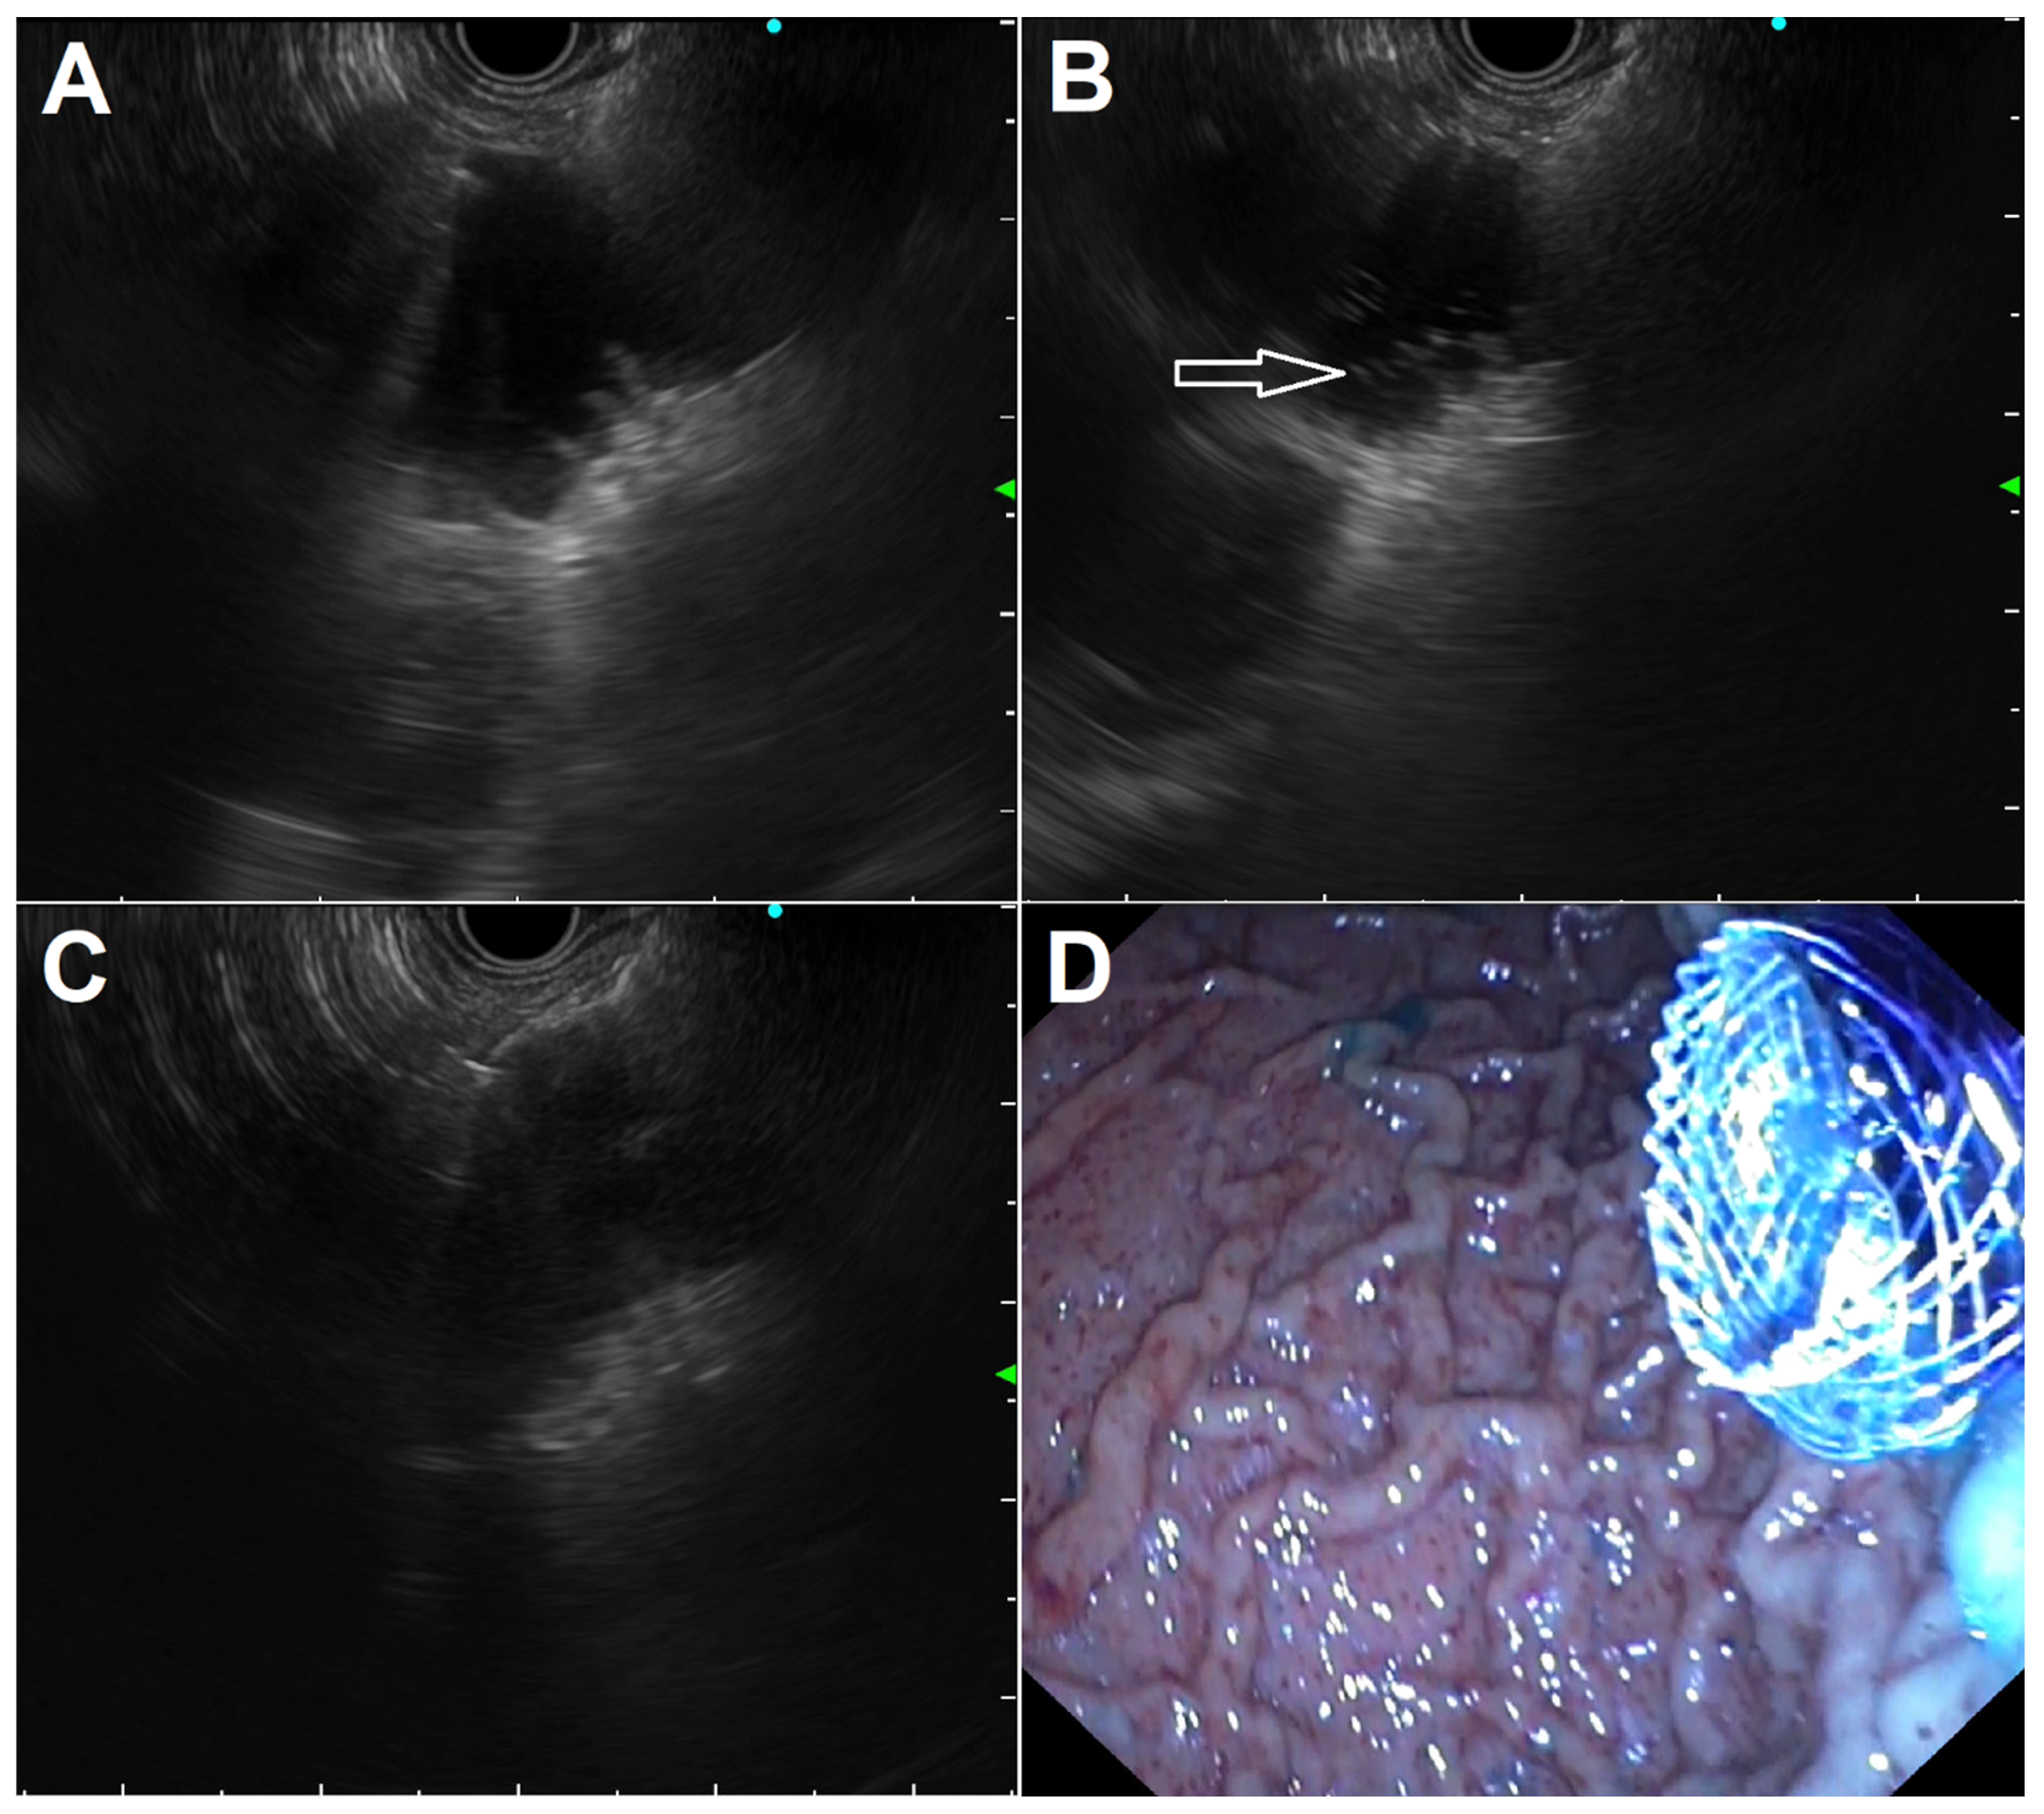

In the WEST technique, a nasoenteric tube is advanced over a guidewire through the stricture into the small bowel distal to the GOO to fill the loop with saline and, using the nasobiliary catheter as a guide, LAMS placement is performed utilizing a free-hand technique (Figure 2). A variation of the WEST technique is possible when the stricture is short and incomplete; the small remaining stricture opening allows the injection of a 500–600 cc solution of saline, contrast, and blue dye by placing the tip of a standard endoscope into the stricture, with fluids instilled to distend the loop distal to the obstruction. The endoscope is then exchanged for an echoendoscope; once the proper loop is identified, it is punctured with a 22G needle to confirm the return of a blue solution and the needle is exchanged for a LAMS to complete the procedure (Figure 3).

Figure 3.

Standard steps in performing EUS-guided gastroenterostomy in a patient with a short and incomplete duodenal stricture leaving a small opening: (A) jejunal loop identification after its proper distension with saline mixed with contrast and methylene blue; (B) cystotome tip (arrow) advancement after cut with pure current for obtaining intrajejunal access; (C) distal flange deployment under EUS guidance; (D) endoscopic view of the proximal flange after deployment under EUS/endoscopic control, with spilling of blue-colored fluid indicating proper stent placement.